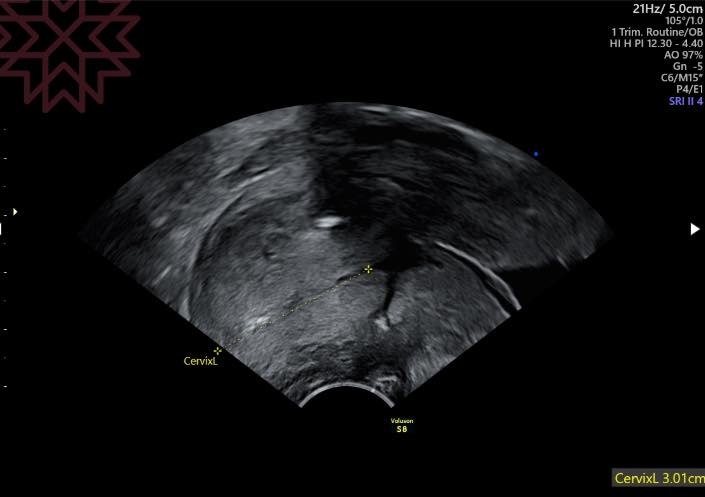

媽咪回診

子宮頸3公分

(第二張圖

或許你應該可以看到亮亮的線頭在哪裡吧?☺️

我們應該過關了